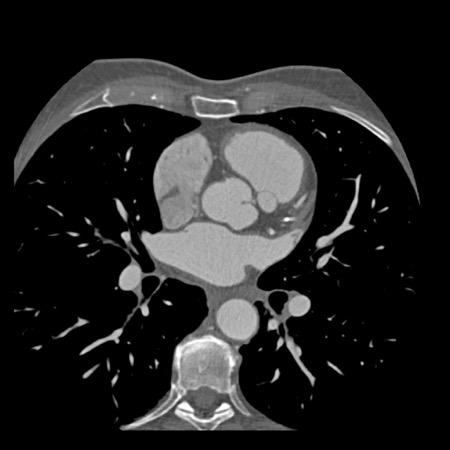

The findings are:

- Moderate (50-69%)

stenosis in the proximal LAD caused by a non-calcified plaque. - Variant of

sinoatrial (SA) nodal artery. The artery usually arises from the RCA as a second

branch after the conus artery, however in this case it arises from the LCX,

courses behind the aorta, anastomosing with the right atrium and with a small

branch supplies the SA-node of the heart. - Thrombus in the

apex of the left ventricle. - CTP was performed

in this patient. CTP showed a perfusion defect at stress imaging in the

territory of the LAD (I+), at rest no perfusion defect was visible.

This patient classifies as CAD-RADS 3/P1/I+, which means

this patient requires further investigation.